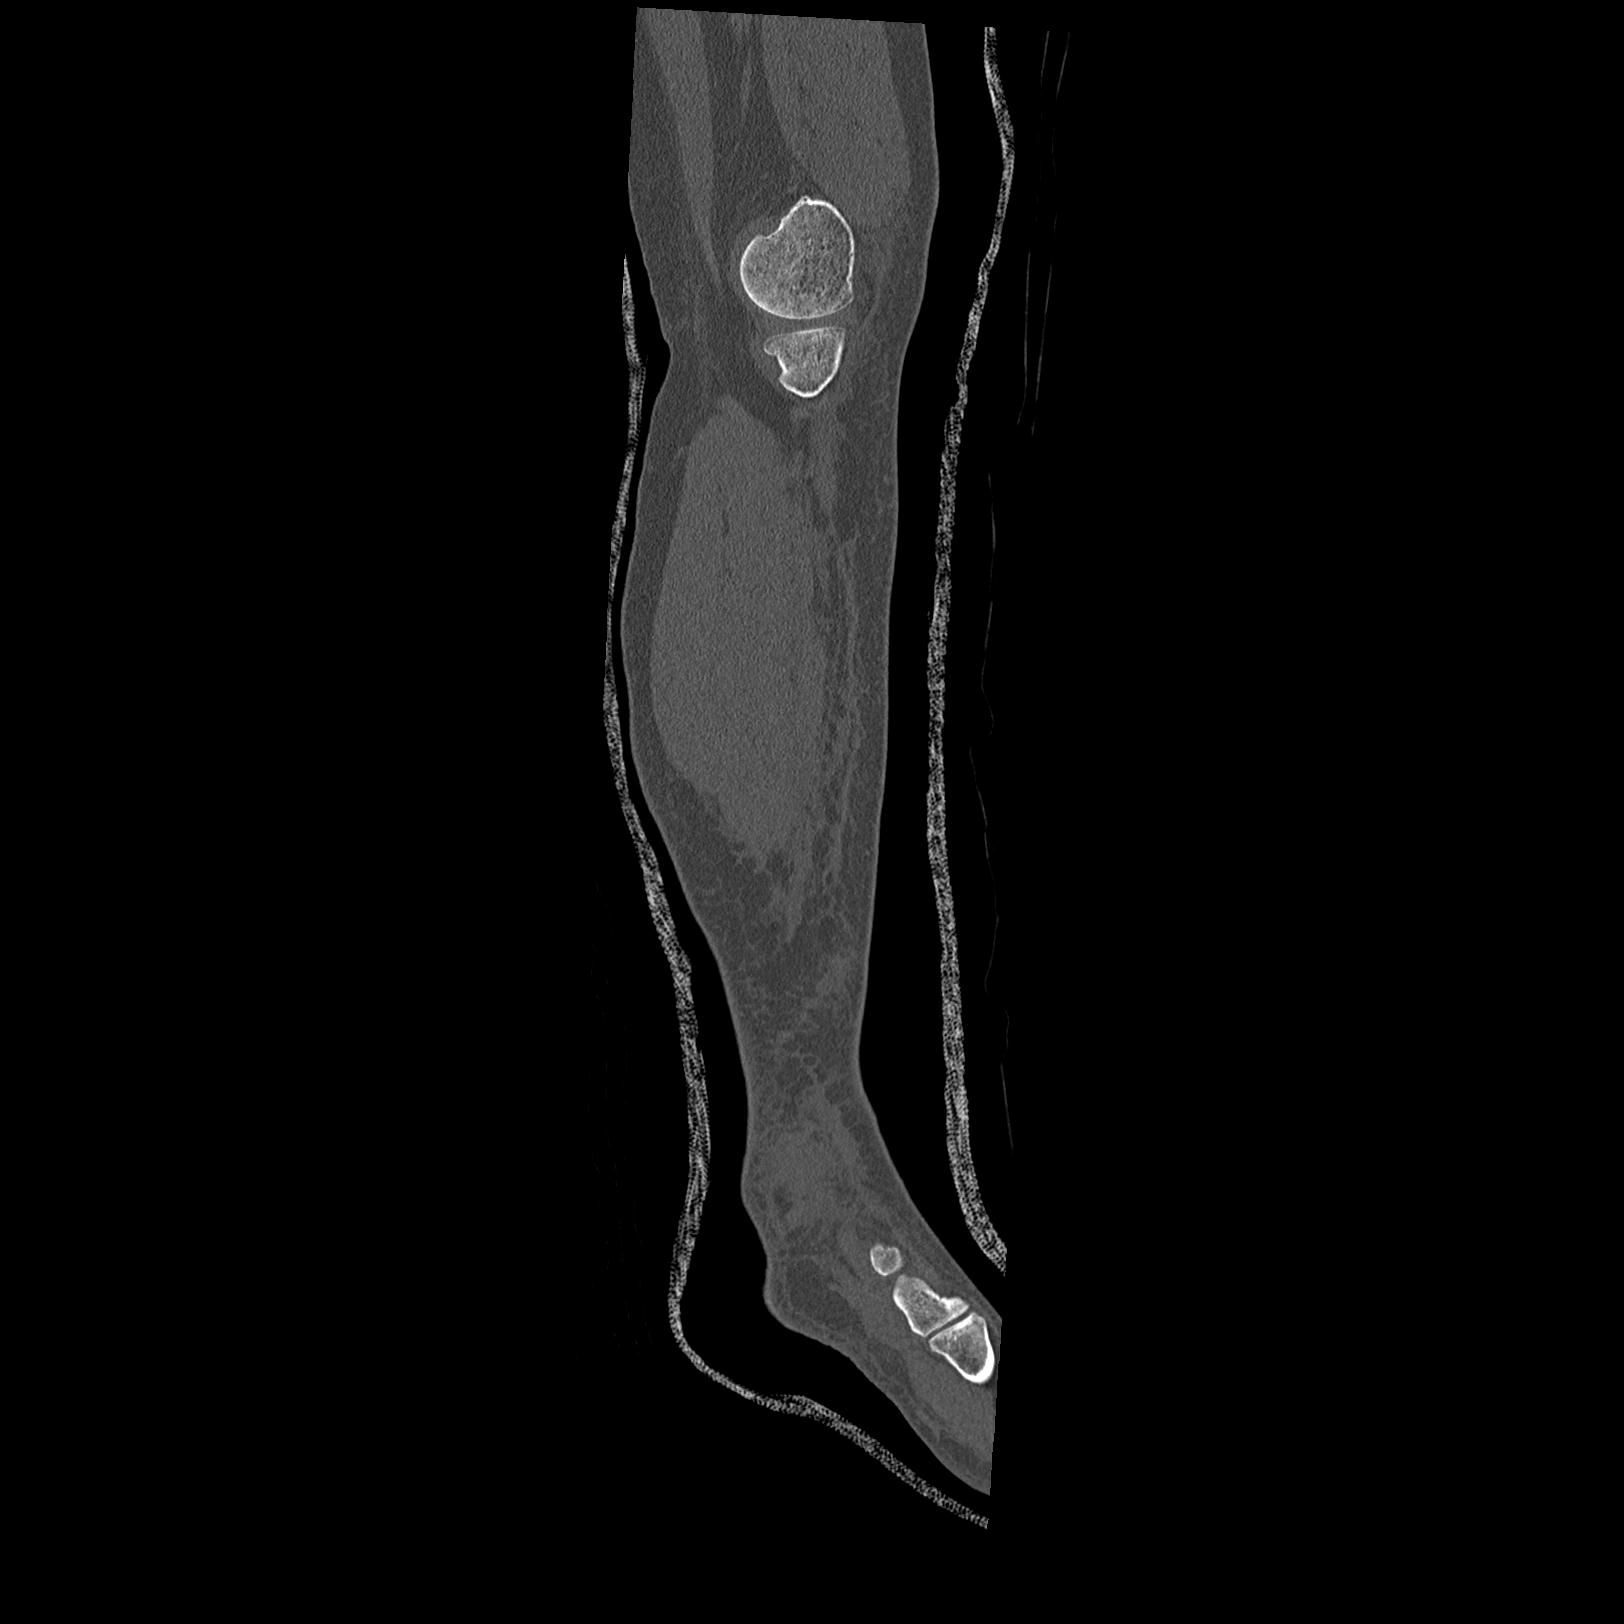

56476 8/28 4R 1/21 2R 左足関節 デジカメ写真 72歳女性 右足関節AS